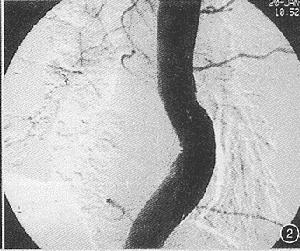

根據腹痛、消化道出血、黃疸及右上腹搏動性腫塊等特徵性表現,結合病史的分析,最後借選擇性肝總動脈造影或腹腔動脈造影確立診斷。

上消化道X線造影,可有胃幽門部或十二指腸被推壓和移位徵象。確立診斷必須依賴於選擇性腹腔動脈造影。腹部平片有時可見蛋殼樣動脈瘤壁鈣化影核素肝掃描可區分肝組織和動脈瘤體間的關係。